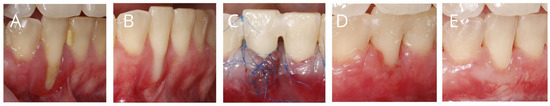

3.2. The Specific Nature of Recession Coverage Procedures in the Context of Potential Postoperative Infection

- Mazzotti, C.; Mounssif, I.; Rendón, A.; Mele, M.; Sangiorgi, M.; Stefanini, M.; Zucchelli, G. Complications and Treatment Errors in Root Coverage Procedures. Periodontol. 2000 2023, 92, e12468. [Google Scholar] [CrossRef]